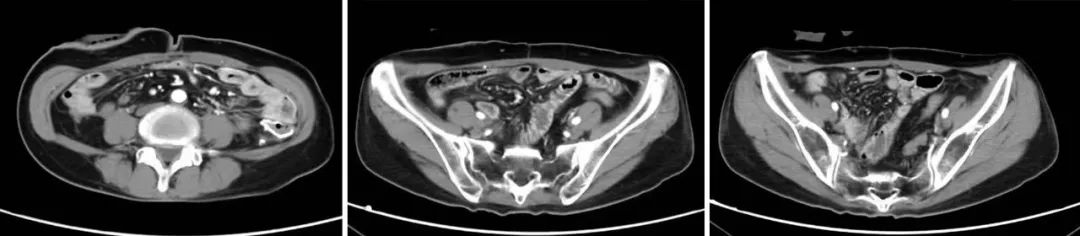

51岁女性恶性腹膜间皮瘤患者,在经过多手段联合治疗后已存活四年,且生活质量如常人。

该患者在4年前经穿刺活检确诊恶性腹膜间皮瘤,经系统性全身治疗后病情仍进展,出现乏力、恶心、呕吐、腹痛等症状,检查提示广泛腹膜病变,大网膜病变尤其明显,呈大饼状覆盖在胃肠道表面,合并血性腹水。患者全身状况较差,存在营养不良、贫血、水电解质紊乱、感染等情况。为了更好地控制病情,患者在对症支持治疗的基础上,接受了经动脉导管灌注化疗联合载药微球栓塞治疗(D-TACE)、腹腔热灌注综合治疗及靶向药物治疗。经上述治疗后,患者肿瘤负荷明显减小,病情逐渐好转,稳定后采用抗血管生成药物、中成药维持治疗。为了进一步控制病情,患者于今年4月接受了肿瘤细胞减灭术治疗,术后采用相关治疗,目前恢复良好。